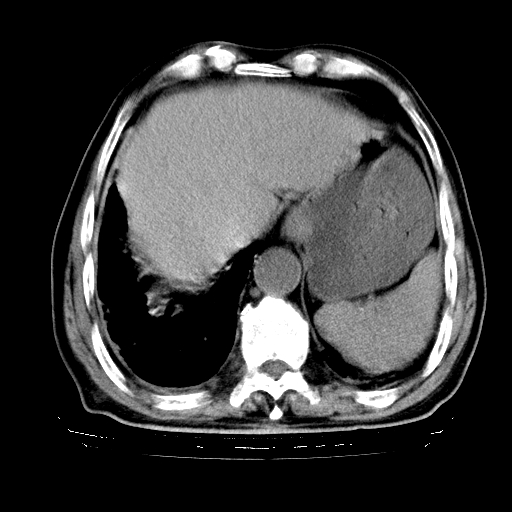

标题: CT25149:男,69岁,反复咳嗽、咳痰五年余,呼吸困难三天。 [打印本页]

男,69岁,反复咳嗽、咳痰五年余,呼吸困难三天。

慢支伴感染、肺气肿、肺心病

慢支伴感染、肺气肿、肺心病!支持!另:间质纤维化!

慢支伴感染、肺气肿、肺心病。双肺间质性改变(间质纤维化)。